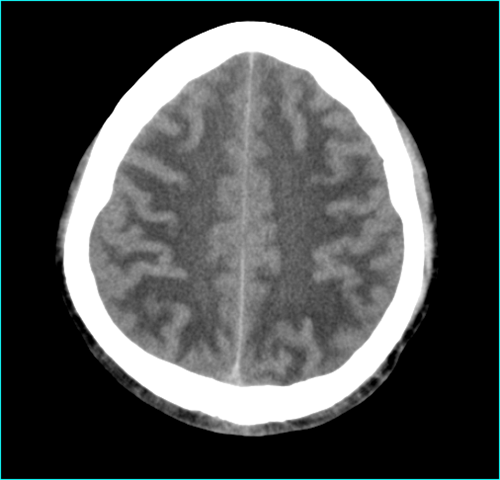

核心概念: 脑梗塞,我们常说的“中风”或“缺血性卒中”,是指因脑部血管阻塞,导致局部脑组织缺血、缺氧而发生坏死,简单说,就是大脑的某条“水管”(血管)堵了,导致下游的“土地”(脑组织)干死了。

“多发”的含义: “多发”意味着在头颅CT或MRI(磁共振)上发现了两个或以上的梗死灶,这些梗塞灶可能位于大脑的不同区域,说明脑血管的阻塞不是一次性的,而是反复发生的。

病因: 主要原因是动脉粥样硬化,就像家里的水管用久了会结水垢一样,大脑的血管也会因为高血压、高血脂、高血糖、吸烟等因素,导致血管壁上形成斑块,这些斑块一旦脱落或破裂,就会形成血栓,堵塞远端的血管。 心房颤动(房颤)等心脏疾病产生的栓子脱落,也是脑梗的重要原因。